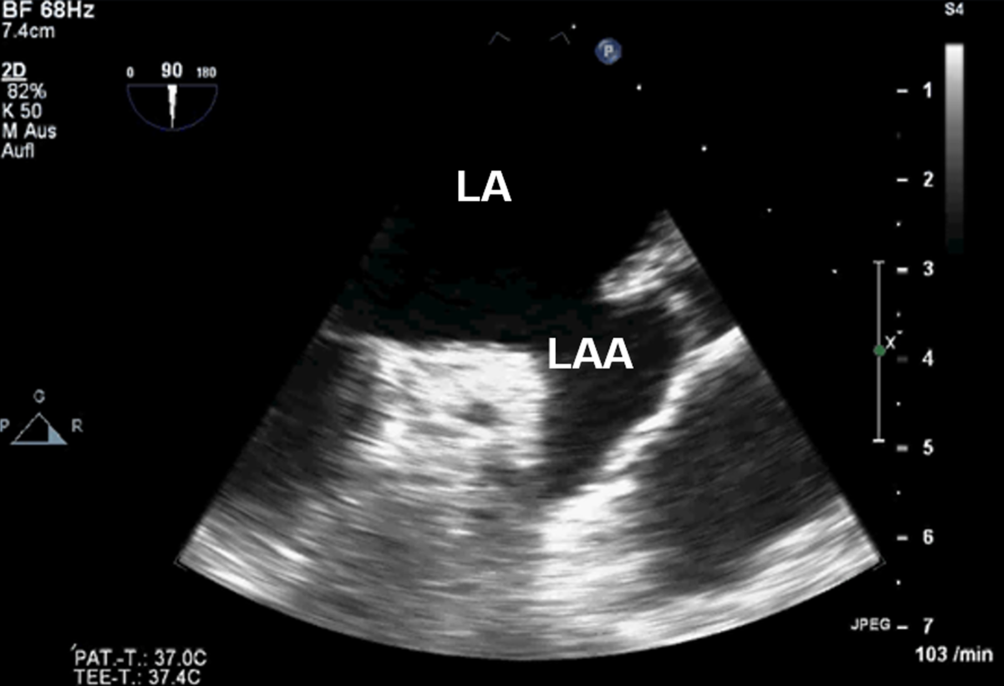

Anlotebene: linkes Vorhofohr

Sondenposition: mittösophageal (ggf. leichte mechanische Längsrotation der Sonde nach links gegen den Uhrzeigersinn)

Rotationswinkel: 45-60-90-135°